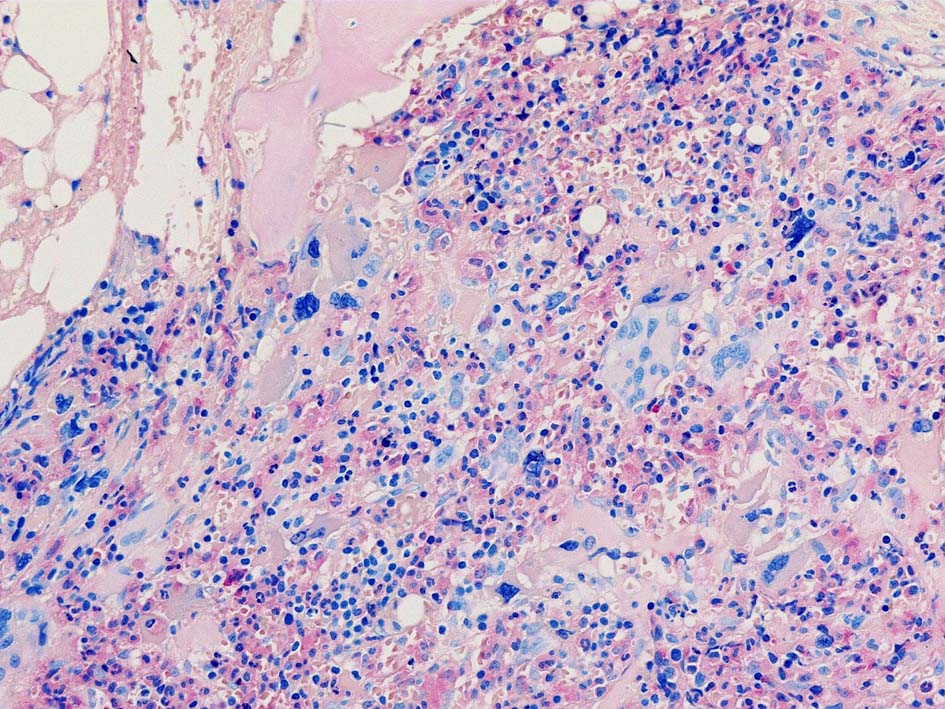

Case02; Meylofibrosis, overt fibrosis

77year-old female. 40歳時polycythemia veraと診断されていた.

黒染する弾性線維の増生のほか, 赤く染まる膠原線維の増生が確認される. MF-2 fibrosis. 鍍銀染色の核染色をすると膠原線維の赤染がわからなくなるので行わない.